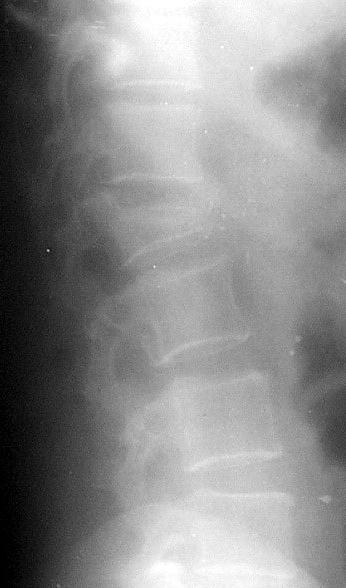

Какие изменения в позвоночнике вы видите на данной рентгенограмме// Болезнь Бехтерева// Деформирующий спондилез// +Остеохондроз// Межпозвоночная грыжа поясничного отдела// Гемангиома тела позвонка